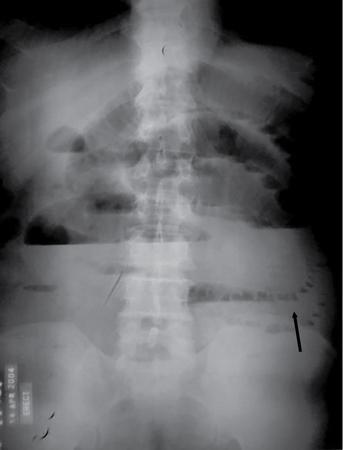

UNDERSTANDING THE ADULT ABDOMINAL RADIOGRAPH: TECHNIQUES AND INTERPRETATION Tanvi Modi Radiography of the abdomen is a common practice for the evaluation of abdominal organs. The anatomy and pathology of digestive, hepatobiliary and genitourinary systems can be assessed using radiographs, either as a stand-alone practice or as a primary imaging modality followed by contrast studies, ultrasound or cross-sectional imaging. In addition, abnormalities of the musculoskeletal or integumentary system can also be deduced on the basis of abdominal radiographs. This chapter intends to give an overview on the techniques and positioning in abdominal radiography as well as interpretation of normal and abnormal features. While superior imaging modalities such as ultrasound, computed tomography (CT), magnetic resonance imaging, capsule endoscopy and the likes have taken over abdominal imaging by and large, radiography still holds a pivotal role in certain situations and conditions, such as: The standard abdominal radiograph is taken in supine position and anteroposterior projection. This is also popularly known as the KUB (kidneys-ureters-bladder) radiograph. Previously, supine as well as erect radiographs were performed in all patients; however, this is not commonly done due to high-radiation dose. For all indications of abdominal radiography, including acute abdomen, supine radiographs are sufficient in terms of radiographic diagnosis, with the exception of perforation for which an erect chest or lateral decubitus radiograph can be performed if there is clinical suspicion. Patient should lie supine on the imaging table with median sagittal plane at right angles to the table and coincident with the midline of the table (Fig. 7.1.1.1). The body is divided into equal right and left halves by the median sagittal which passes through the sagittal suture of the skull. Pelvis should be adjusted so that the anterior superior iliac spines are equidistant from the table top. Gonadal shields, in the case of male patients, should be placed with the upper edge of the shield at the level of pubic symphysis. Although rarely used for female patients, these should be positioned between the anterior superior iliac spines and the pubic symphysis. The centre point of the image receptor should be approximately located at a point 1 cm below the line joining the iliac crests. The X-ray beam should be in a vertical direction, perpendicular to the table top and image receptor at the centre point. Collimation should be such that the soft tissue and subcutaneous region along lateral aspects of the abdominal cavity should be covered within the image. Also, the superior extent involving diaphragm and inferior extent involving the inferior pubic rami is important to look for any lower chest pathologies or any inguinal hernia. 35 × 43 cm (14 × 17 inches) in portrait orientation. On an average, abdominal radiograph exposes a patient to a dose of approximately 1.5 mSv, which is equivalent to 75 chest radiographs or 1/6th dose of a standard CT of the abdomen. The entrance skin dose is approximated to be 4 mGy. At such an effective dose, the additional lifetime risk of fatal cancer is 1 in 30,000. The exposure time is kept short. Patient is asked to exhale completely and hold their breath, with exposure taken at this point of full expiration to ensure imaging of abdominal organs in their natural positions. Modifications of this technique can be made depending on patient habitus and clinical condition. Kilovoltage peak (kVp) should be set to allow adequate visualization of abdominal soft tissue structures as well as semiopaque renal and biliary calculi. Average kVp is set at 70–85 kV. 102 cm (40 inches) Grids are commonly used to reduce scatter radiation. Placement of side marker on the image receptor at the time of radiographic exposure is essential. Bowel pattern depiction should be such that there is minimal lack of sharpness. Standard guidelines for abdominal radiography dictate that the radiograph should extend from the diaphragm up to the level of inferior pubic rami and must include the lateral abdominal wall musculature. The abdomen is divided into four quadrants on the basis of two perpendicular lines (Fig. 7.1.1.7). The vertical line passes through the mid sagittal plane and crosses the umbilicus and symphysis pubis. The horizontal line is a transverse line across the umbilicus at 90 degrees to the vertical line and is situated at the level of L4–L5 intervertebral disc. The quadrants are as follows: Another division system is dividing the abdominopelvic cavity into nine regions using two vertical and two horizontal planes (Fig. 7.1.1.8). The vertical planes, also known as the right and left lateral planes, are parallel to the midsagittal plane between midline and anterosuperior iliac spines on either side. Of the two horizontal planes, the upper transpyloric plane is at the level of lower border of L1 and the lower transtubercular plane is at the level of L5. The nine regions are: On a standard radiograph, the exposure should be such that the stomach, bowel loops, outlines of liver, spleen, kidneys, psoas muscles should be well identified. Also, lumbar transverse processes should be seen. Arch of the pubic symphysis should be visible to evaluate bladder region. A well-centred film without rotation will demonstrate bilaterally symmetrical lower ribs, iliac wings, ischial spines and obturator foramina. Different structures seen on an abdominal radiograph can be classified into five basic densities: Identification of different structures depends on the relative degree of contrast between their densities. The demarcation is clearer in chest and is diminished in abdomen due to relative similar soft tissue density of various structures. On a normal radiograph, relatively large amounts of gas in stomach and colon with minimal small bowel gas can be seen. Further, colonic gas can vary from negligible to extensive, mimicking obstruction pattern; however, usually the gas is enough to delineate colonic haustral pattern. Faecal matter gives a mottled appearance to colonic gas. Short-air fluid levels on an erect radiograph may be seen even in normal cases. The normal appearance of small bowel loops on an abdominal radiograph follows the rule of threes: Stomach is seen in the left upper quadrant and is visualized when distended with air. It is commonly seen extending from T11 to L2 level. Common feature identifying the stomach is the fundal gas which is usually seen as an air fluid level within the gastric lumen. Small bowel loops are distributed to the centre of the abdominal cavity and large bowel loops are peripheral. Duodenum is predominantly situated in right upper quadrant. It extends to left upper quadrant in the region of duodenojejunal flexure. Jejunum occupies the left upper and lower quadrants and is easily identified due to the presence of thick, numerous, closely spaced valvulae conniventes (Fig. 7.1.1.9A). The ileum occupies both lower quadrants and extends into right upper quadrant. Ileum has few and less prominent valvulae as compared to jejunum (Fig. 7.1.1.9B). Ascending and descending colon are retroperitoneal and have relatively fixed positions along lateral aspect of the abdominal cavity on either side. Transverse and sigmoid colon, on the other hand, may have a variable position due to their mobility along mesocolon and redundant pattern. These can be identified with confidence on account of haustrations and faecal matter (Fig. 7.1.1.10). Haustrations are usually well seen in ascending and transverse colon and poorly delineated beyond splenic flexure. Caecum is in the right lower quadrant, though it may be mobile or pulled up. Rectal gas is usually seen in the midline at the level of pelvis and its presence rules out large bowel obstruction. All these positions may vary due to anatomical conditions such as malrotation or pathological conditions, for example volvulus. Liver, spleen and renal outlines cannot be completely traced with precision due to the overlap by bowel loops. On a frontal projection, the liver appears as a triangular structure occupying right and left hypochondrium and epigastric region. Occasionally, the right lobe may be seen extending lower than the right renal shadow. This is a normal variant known as Reidel’s lobe. Gall bladder is situated in the posterior and inferior region of the liver and any pathology of the gall bladder should be looked for in this region. On a lateral radiograph, the gall bladder is anterior to the midcoronal plane. This helps in distinguishing gall bladder calculi from renal calculi, which will be more posteriorly situated. Spleen is seen in left upper quadrant/left hypochondrium, flushed to left lower ribs and left hemidiaphragm. Pancreas is present in the epigastric region (right and left upper quadrants) and is usually not identified in the absence of a pathology. The kidneys are bean-shaped retroperitoneal organs which are seen on either side of the vertebral column and lateral to psoas muscles. Due to the presence of liver on the right side, this kidney is slightly lower in position as compared to its contralateral counterpart. The visualization of kidneys on radiographs is facilitated by the surrounding fatty capsule. Kidneys lie between T11–12 and L2 level, with left kidney 1 cm higher than the right. Psoas muscle shadow can be normally seen along lateral aspect of lumbar spine bilaterally and is mildly concave (Fig. 7.1.1.11). Abdominal wall muscles are not routinely assessed on radiography; however, inclusion of lateral abdominal wall (muscles as well as subcutaneous plane) is a must while performing radiography. The flank stripe or the properitoneal fat stripe is a fat density linear concavity seen along lateral abdominal wall (Fig. 7.1.1.11). It is bound by the paracolic gutters and air-filled ascending and descending colon. All the solid organs in the abdomen are identified due to the fat density outlining them. Distortion of these fat lines helps in identifying organomegaly or focal mass lesions. The dome of urinary bladder is outlined by fat, which aids in differentiating its density from other soft tissue structures of the pelvis. Not all calcifications seen on abdominal radiograph are abnormal. Some may depict age-related changes such as vascular calcifications involving abdominal aorta, pelvic vessels, splenic artery in the region of left upper quadrant. Within the pelvis, phleboliths may be seen and mistaken for urinary calculi. Assessment of lumbosacral spine, iliac bones and femoral heads can be made on the basis of plain radiography. Degenerative changes may be commonly seen. Lower ribs can also be evaluated for pathologies. Dilated small bowel loops with rounded soft tissue density in midline over umbilical region suggests obstruction secondary to umbilical hernia. Pneumoperitoneum must be looked for in all cases of acute abdomen. While erect chest and left lateral decubitus radiographs can detect even 1 mL of free air, there are multiple signs on supine radiograph to suggest this diagnosis, for example Rigler’s sign, falciform ligament sign, football sign (Figs. 7.1.1.24 and 7.1.1.25). Retroperitoneal perforation may demonstrate air outlining psoas muscles and retroperitoneal organs. Small amount of free air may persist in the abdominal cavity up to 3 weeks after surgery, although it usually resolves within a week. Clinical history is important in such cases. Air foci within the bowel wall may represent bowel ischaemia/strangulation. Linear gas patterns in right hypochondrium may be due to two causes, that is pneumobilia and pneumoporta. The former can be seen normally postbiliary surgery, sphincterotomy, ERCP or in the case of abnormal fistulous communication between bowel and biliary tree (Fig. 7.1.1.26A). Pneumoporta (Fig. 7.1.1.26B) is a red flag and warrants further investigation to look for conditions such as mesenteric ischaemia and toxic megacolon. Pneumobilia is more centrally located whereas air shadows in pneumoporta are seen reaching up to periphery of liver. Air foci over renal shadows (Fig. 7.1.1.27), gall bladder or pancreas, in the absence of recent procedural history, suggest fulminant infection and mandate urgent intervention. Central midline calcific foci between T9 and T12 vertebrae can be attributed to calcific pancreatitis (Fig. 7.1.1.28). In the left upper quadrant, areas of calcification seen involving a shrunken spleen may be seen in autosplenectomy. In right upper quadrant, calcified gall stones may be seen. These tend to be small, multiple, uniformly circumscribed and ring-like in appearance with central translucency (Fig. 7.1.1.29A). Mercedes Benz sign, a triradiate pattern of gas lucency, is associated with gallstones. In contrast, renal calculi are more commonly solitary, irregular, of homogenous density, conform to renal calyceal or pelvic outline (Fig. 7.1.1.29B) and are sometimes of staghorn configuration. On lateral view, the gall stones are more anteriorly located as compared to renal calculi, which may be partly superimposed on lumbar vertebrae. Ureteric calculi tend to overlap bony structures such as lumbar transverse processes (Fig. 7.1.1.29B) or sacroiliac joints. Extensive or patchy, curvilinear calcification of gall bladder wall is known as porcelain gall bladder which is often associated with malignant transformation. Calcification involving adrenal glands may be secondary to infection or haematoma, or a congenital condition known as Wolman’s disease where there is bilateral involvement. Discontinuous discrete midline tram track calcification in the abdomen may indicate atherosclerotic changes in abdominal aorta and branch vessels. However, when the calcification is in a globular pattern and seen below the level of L2 vertebra, aortic aneurysm should be suspected (Fig. 7.1.1.30). Appendicoliths, though not commonly seen, may sometimes be detected in right iliac region. Pelvic calcifications: vesical calculi, distal ureteric or vesicoureteric junction calculi, calcified fibroids, ovarian dermoid with tooth-like calcifications (Fig. 7.1.1.31) may be the cause of abdominal pain and should be diligently looked for. Vesical calculi are usually more large and central in location whereas calcification due to fibroids may be more lateral. Schistosomiasis is another cause of bladder wall calcification, as is calcification of bladder tumours. Phleboliths tend to be bilaterally symmetrical, with a lucent centre unlike ureteric calculi. While it is believed that phleboliths are located below the level of ischial spines and ureteric calculi above, this is not always true and should be confirmed with CT. Fluid may collect adjacent to properitoneal fat line, forming a linear soft tissue density separating the fat line from the ascending or descending colon. Hellmer’s sign demonstrates medial displacement of lateral edge of liver (hepatic angle), due to fluid collection or ascites. Gross ascites may appear as generalized abdominal haziness or diffuse increased density of pelvis. Abscesses can involve any solid organ and in such cases may be difficult to demonstrate on plain radiography alone. Enlargement of organ or faint gas densities within can be suggestive of the same. In the case of peritoneal abscess, mottled density due to air, fluid and necrotic contents point towards this diagnosis, especially in right iliac fossa in association with appendicitis. Retroperitoneal abscess, similar to any retroperitoneal mass, may cause displacement of retroperitoneal structures (Fig. 7.1.1.32). Subdiaphragmatic abscesses may show concomitant ipsilateral pleural effusion (Fig. 7.1.1.33). These should be differentiated from Chilaiditi syndrome. Fluid and soft tissue lesions present with the same density on radiographs. While it is difficult to characterize the lesion and organ of origin, clues for the same can be provided by organomegaly (Fig. 7.1.1.34), distortion of fat surrounding solid organs, displacement of bowel loops or solid organs. For example, a retroperitoneal lesion may cause anterior or inferior displacement of kidney, a pelvic mass may cause upward displacement of small bowel loops. Different densities such as fat or calcification may help in identifying organ of origin (e.g. fat and tooth densities seen in ovarian dermoid). Convexity of margins of psoas muscle on an abdominal radiograph can be due to haematoma, abscess or intramuscular tumour. Radiographs are performed for the initial diagnosis of foreign body in the abdomen including type, number of foreign bodies, location, size and shape (Fig. 7.1.1.35). Radiolucent foreign bodies such as wood, plastic, chicken bones will not be easily identified on radiography. Low kVp (65–70 kVp) can increase contrast and help identify these objects. In addition to an abdominal radiograph, chest radiography is also performed to exclude aspiration or oesophageal location of foreign body. Ingested or introduced foreign bodies may cause complications such as obstruction, perforation, fistula formation and sepsis. Hence, once their presence is confirmed, follow up radiography must be performed until they are eliminated. One must look for fractures/dislocation injuries involving the vertebrae or pelvic bones, especially after history of trauma. Lucent expansile lesions or sclerotic bony deposits which represent neoplasms, absent pedicle sign in cases of metastasis, metabolic bony changes such as rugger jersey appearance, Paget’s disease, arthropathies such as ankylosing spondylitis with bamboo spine appearance and sacroiliitis (Fig. 7.1.1.36) are some of the conditions which may be diagnosed based on an abdominal radiograph. Overlap of bowel loops over iliac blades may lead to a misdiagnosis of lucent lesions and should be evaluated with caution. Basal pneumonia may be the cause of acute abdominal pain and should be looked for in abdominal radiography. Similarly, pleural effusion, pericardial effusion, calcified pleural plaques, achalasia, interstitial fibrosis are few other findings that can be seen in lower chest on an abdominal radiograph. Basilar atelectasis can give a deceptive appearance of pneumoperitoneum (Fig. 7.1.1.37). Surgical clips, commonly in right hypochondrium after cholecystectomy, drainage tubes, ventriculoperitoneal shunts, femoral line catheters, IVC filters, stents (vascular, renal, biliary) (Fig. 7.1.1.38), stoma bags, contraceptive devices are some structures that may be seen in an abdominal radiograph. Correct knowledge of patient history and normal locations of these structures prevents misdiagnosis. Certain artefacts may be projected upon the radiograph due to surface structures such as trouser buttons, body piercing, sequins over clothing and should not be considered as a pathology. Multiple skin surface nodules in cases of neurofibromatosis, soft tissue focal swellings, such as abscesses, lipomas, haematomas, desmoid tumours and malignant lesions may be incidentally seen on radiography. These can be further evaluated using ultrasound or CT. Subcutaneous emphysema is another finding that may be seen in lower abdominal wall secondary to retroperitoneal perforation or diffusely along abdominal wall in the case of bowel perforation (Fig. 7.1.1.39). Foreign bodies such as bullets and pins may be seen lodged in abdominal wall. A systematic approach to abdominal radiographs is important for accurate diagnosis as follows: Despite the development of newer techniques for imaging of the abdomen, plain radiography still holds an important place in the initial assessment of acute abdomen. Positive and negative findings on an abdominal radiograph can direct further investigation. Ideal positioning, recognition of normal appearances and keen scrutiny for pathologies is a sine qua non for radiologists reading a plain film of the abdomen. OESOPHAGOGRAM Padma V. Badhe, Vikram Reddy, Sultan Moinuddin Shaukatali, Zillani Alam, Ravi Varma, Abhishek Bairy, Dasari Ravikiran, Revati Tekwani, Soniya Patankar, Megha Nair, Gautham Shankar Oesophagogram is the process of obtaining radiological images and simultaneous motion recording to evaluate function and disorders of pharynx, oesophagus and proximal stomach. Oesophagogram is usually done primarily to evaluate dysphagia. Some of the common indications are oesophageal motility disorders, strictures, gastro-oesophageal reflux disease (GERD) and suspected masses. It can also be used to detect uncommon anomalies like vascular rings/slings and aberrant anatomy. It also helps to evaluate further in cases where there is inability to pass upper GI scope. Double-contrast oesophagogram is mainly indicated in early mucosal disease like erosion, polyp, infection and tumours. If a motility disorder is suspected, dynamic technique (e.g. videofluoroscopy) is used for dysphagia or aspirations in cases of stroke, neuromuscular disorders, post head and neck surgery or radiation. Barium oesophagogram is contraindicated in suspected cases of perforation and tracheoesophageal fistula, aspiration, rarely if there is hypersensitivity to barium suspensions. It is also contraindicated in suspected oesophageal perforation where a water-soluble contrast agent is more suitable. However, ionic water-soluble contrast agent is better avoided in cases of aspiration or fistula with airway. The contrast examination of the pharynx is dangerous in cases of acute epiglottitis and must be ruled out on plain radiograph. An 80% w/v barium suspension is used in full column views. However, 200%–250% w/v barium suspensions is usually required for mucosal relief films. The barium sulphate mixture is fed to the patient either by spoon, by glass, or through a drinking straw, depending on its consistency. In videofluoroscopy, the pharyngeal phase of swallowing is usually safer with barium pudding than with thick barium and safer with thick barium than with thin barium. However, if the major abnormality is poor pharyngeal contraction leading to stasis in the piriform sinus (and epiglottic tilt is normal), a thin liquid is safer. Epiglottic motility is better assessed with thin barium because thick barium often obscures the epiglottic tip. Fluoroscopic equipment capable of cine fluoroscopy and capability for rapid sequence spot images (high frame rate) is needed for this examination, Barium suspension, straw, glass, Lead apron and radiation protective equipment. The patients are instructed to fast after midnight before the day of the examination. The pharynx should be made as dry as possible during the examination as high-density barium adheres to dry pharyngeal mucosa. Activities like smoking, chewing gum and lozenges must be abstained before the procedure as they impair barium coating by increasing the salivary secretion. Regular oral medications must be taken with sips of water; however, insulin must be skipped on the morning of examination. The major principles of a good oesophagogram includes mucosal coating, distension and projection. A routine oesophagogram consists of screening of the oral, pharyngeal and oesophageal phases of swallowing, single and double-contrast examination of pharynx, single contrast, double-contrast and mucosal relief views of the oesophagus. In cases of dysphagia, the examination is tailored depending on whether the symptoms are either pharyngeal or oesophageal and initial fluoroscopic findings. If patients’ symptoms are suggestive of oral or pharyngeal disorder then pharynx is evaluated first. Similarly, if patient is suspected to have thoracic oesophageal disease then, double-contrast examination of the oesophagus is performed before the pharyngeal evaluation. During an oesophagogram the positioning of the patient varies according to the type of examination (Table 7.1.2.1).